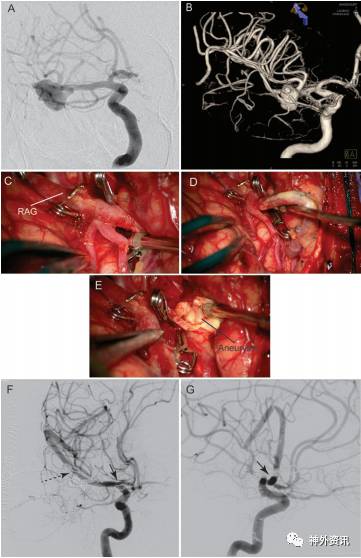

MCA分叉后MCA动脉瘤的治疗设计取决于动脉瘤在MCA的M2上的位置(图2)。可以运用除了EC-IC外所有的搭桥方法,因为动脉远端不需要高流量。最常见的血管搭桥为STA-MCA吻合。在2例患者中,分别进行血管再移植和带蒂血管搭桥,1例原位血管搭桥(图7)。

图7. 分叉后MCA动脉瘤搭桥设计。A.57岁女性患者,颅脑MRI-T1冠状位增强显示右侧MCA远端动脉瘤;B.DSA示动脉瘤位于岛叶M2段,将动脉瘤近端栓塞,远端进行M3-M3原位搭桥吻合;C.闪光荧光技术确定顶后动脉未受累;D.角动脉作为原位供体血管,将两支皮质动脉侧-侧吻合;E.追踪从动脉瘤至皮质表面的输出端动脉,以确定搭桥位置;F.术后血管造影显示动脉瘤完全消失。